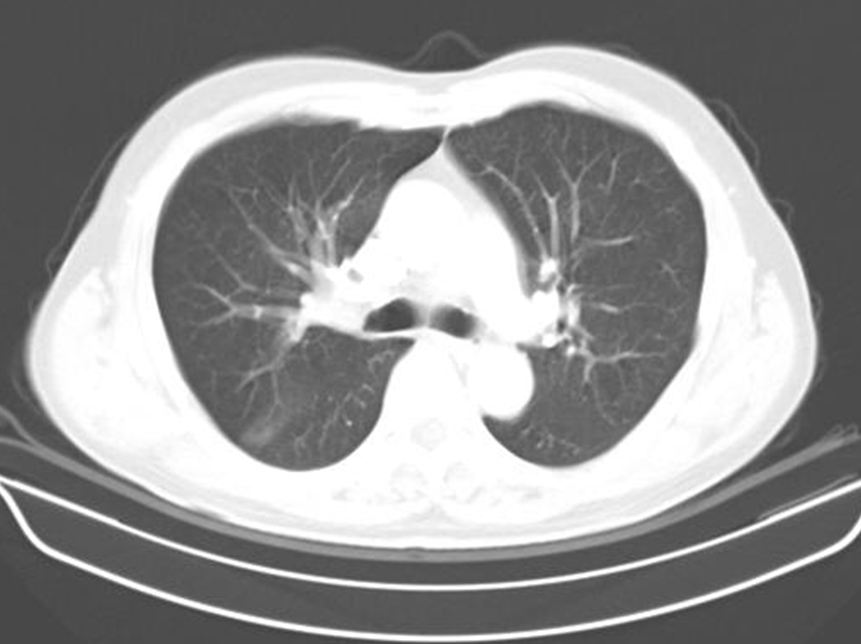

69 ¼¼ ³²È¯

CLL Áø´Ü¹Þ°í  allegenic stem cell transplantation ¹ÞÀº ÀÌÈÄ 8°³¿ù° ¹ß»ýÇÑ  ÇÑ´Þµ¿¾È Áö¼ÓµÇ´Â cough , Blood tingled sputum ÁÖ¼Ò·Î ³»¿øÇÔ

ù¹øÂ° µÎ¹øÂ° ¿µ»óÀº ÇÑ´Þ ÀüÀÇ Chest CT »çÁøÀÔ´Ï´Ù.